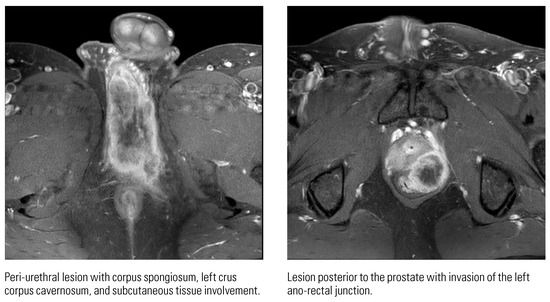

Down the Not So Straight and Narrow: A Rare Case of Primary Urethral Squamous Cell Carcinomas in a Young Patient